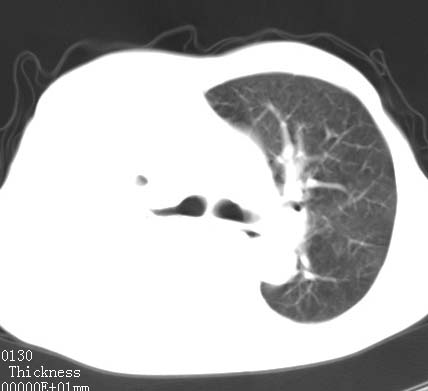

病人女 60岁 咳嗽 气促十余天,大叶性肺炎.

右肺上下叶均见 大片状密度增高影,边界清晰,其内可见支气管充气征,气管支气管通畅。纵膈略向右移位,其内无肿大淋巴结影。首先考虑炎性病变。不排除一些特异性的炎症。不知道发烧吗??wbc高吗??建议治疗后复查!!

看影响还是首先考虑炎性改变,建议实验室检查,还有要警惕炎性肺泡癌,具有的枯枝征象。

看影像还是首先考虑炎性改变,建议实验室检查,还有要警惕炎性肺泡癌,具有的枯枝征象